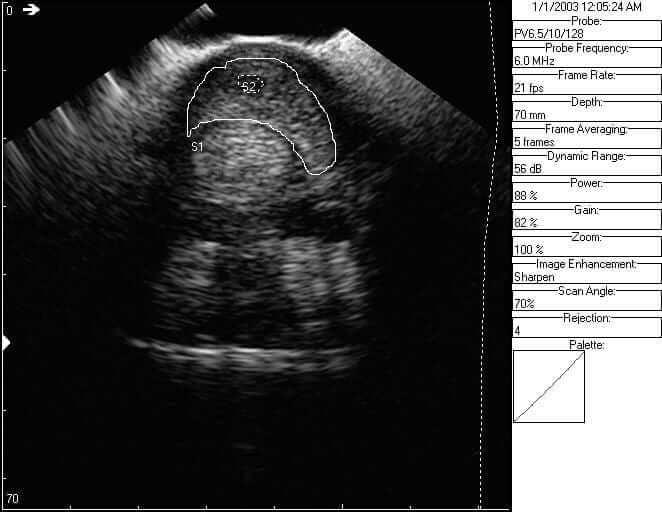

Here is the right front after 18 days of therapy, managing inflammation and enhancing the immune response. This particular horse did not receive any invasive therapies and was on full turnout while receiving the Cur-OST EQ Plus twice daily and the Cur-OST Immune & Repair once daily. The image on the left is the regular image, while the one on the right is the same image, but the tendon areas are outlined for clarification.

At the 18 day mark, the circumference of the superficial flexor tendon is measuring 72.0 mm and core lesion size of 13.1 mm. Overall, in a little over two weeks time, we have reduction in the overall size of the tendon and filling or repair of the central core lesion. The horse was also about 90% sound at the two week mark and under saddle with a controlled trot.